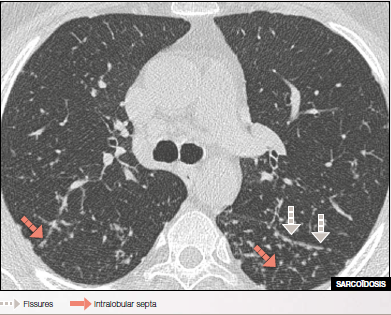

Micronodules with clear outlines & high densities distributed along fissures, peripheral pleura, and intralobular septa.

HRCT shows large sarcoid nodules resembling galaxies associated with enlarged sub carinal lymphnodes.